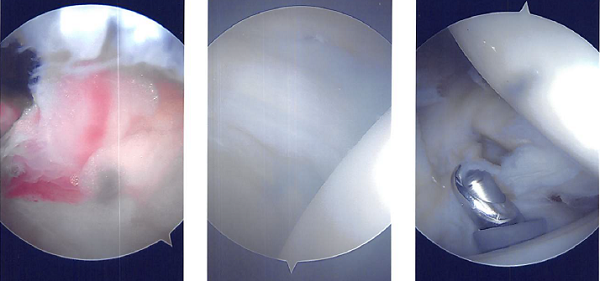

A beanbag held the position, and all of the bone prominences were well-padded. Behind the posterolateral corner of the acromion, a surgical incision was made. The glenohumeral joint was penetrated with the scope. There was a glenohumeral joint examination.

The labral hole was present. Labral degenerations were removed by shaving. The posterior labrum had degeneration, which was cleared out by shaving. There was subacromial bursitis.

Using a shaver, a thorough bursectomy was performed. It was created a lateral portal. The acromion was frayed and had a type 2 (curved configuration) configuration.

Acromioplasty was decided upon. After cleaning with a heat wand and a bur, acromioplasty was carried out. The AC joint was checked after a comprehensive acromioplasty and found to be degenerating. Excision of the distal clavicle was planned. The distal clavicle was removed using a wand and then a bur.

The distal clavicle’s last centimeter was removed. Final images were captured and stored. Nylon #4-0 was used for closure. After being extubated, the patient was taken to the recovery area.